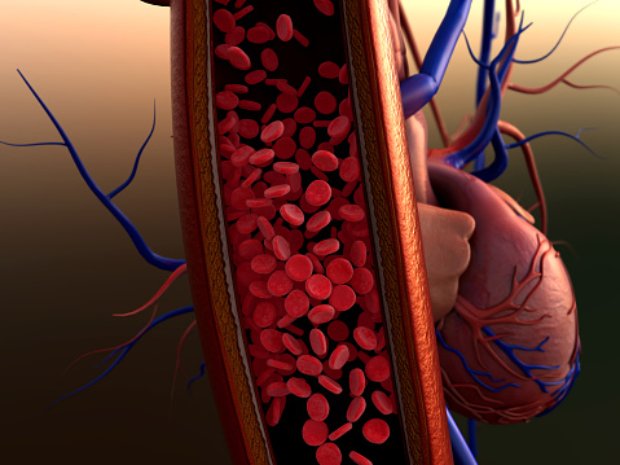

An arterial embolism is a blood clot that has become lodged in the arterial blood system, the main circulatory system for delivering oxygenated blood. This can restrict vital blood flow in tissues and organs virtually anywhere in the body. However, blood clots in the arterial circulatory system tend to affect the arms, legs, or feet ...click here to read more